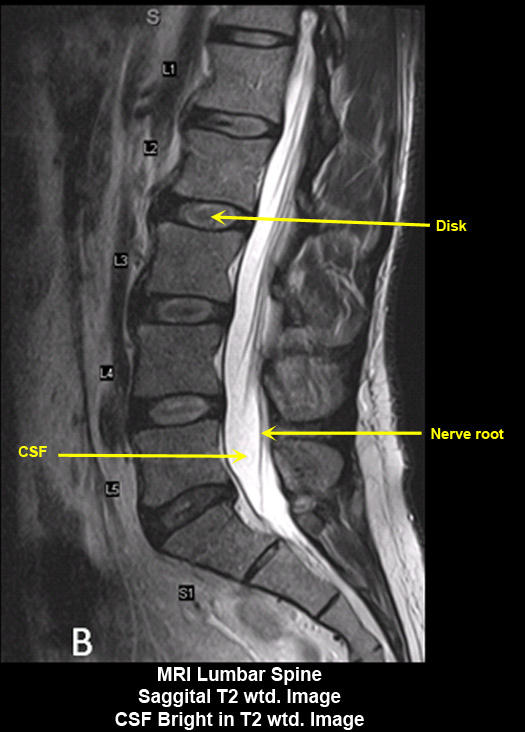

MR Brain and Spine